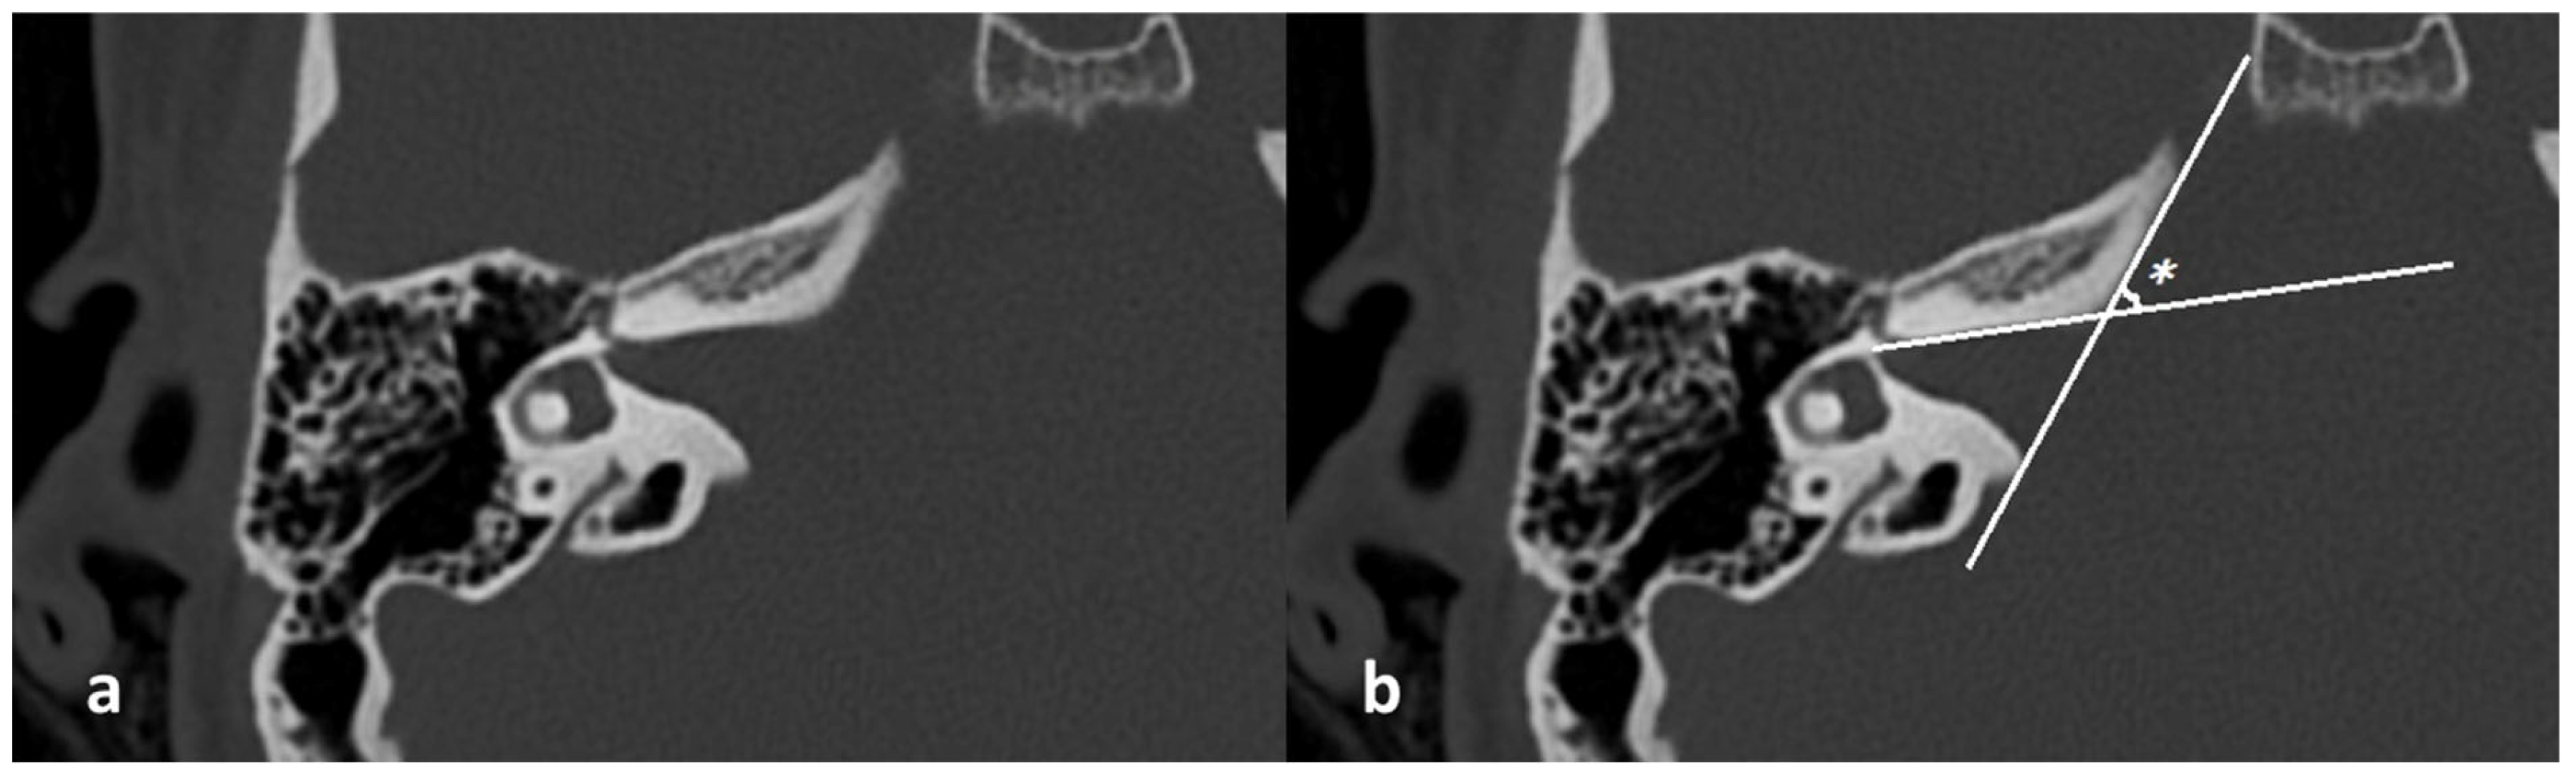

- Right and left lateral angle: the angle between the line tangent to the IAM inlet and the line tangent to the anterior wall of the IAM (Figure 3);